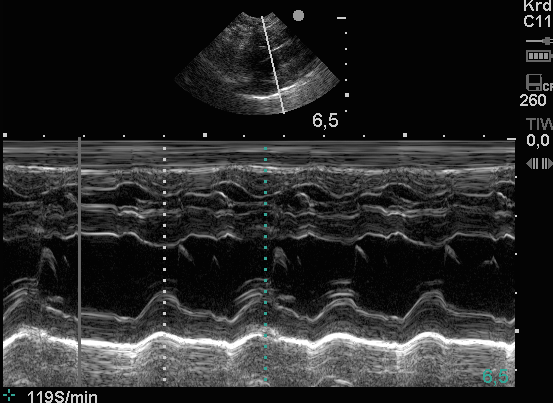

Die oberen beiden US-Bilder zeigen eine Technik, die es dem Untersucher ermöglicht, die Effizienz der Herzleistung darzustellen.